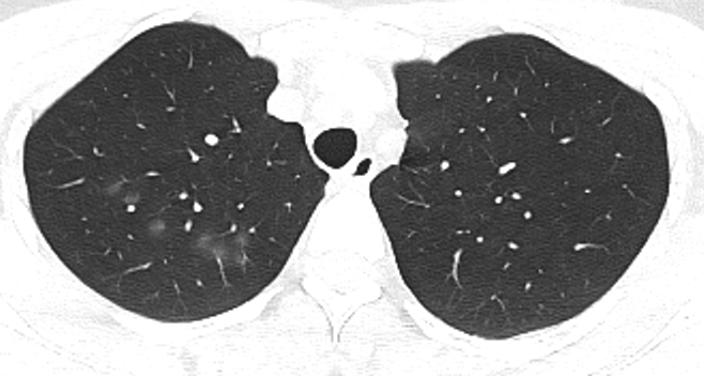

胸部CT示:双肺多发磨玻璃结节,左下叶背段散在实性结节,散在小空洞,部分支气管的管壁增厚,如下(图1~17)。